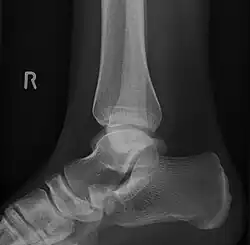

Radiographie du pied montrant un os naviculaire accessoire

Un os naviculaire accessoire est un os accessoire du pied qui se développe parfois anormalement devant la cheville vers l'intérieur du pied. Cet os peut être présent dans environ 2 à 14 % de la population générale et est généralement asymptomatique[1],[2],[3]. Lorsqu'il est symptomatique, une intervention chirurgicale peut être nécessaire.

L'os naviculaire accessoire peut provoquer un étirement continu et une tension sur le tendon postérieur tibial qui peut évoluer vers une douleur chronique invalidante et peut provoquer une rupture du tendon ou une déformation secondaire du pied plat, lorsque cela se produit, cette condition est communément appelée syndrome naviculaire accessoire[4]. D'autres conditions qui imitent étroitement les symptômes d'un os naviculaire accessoire incluent fasciite plantaire, oignons et épine calcanéenne.

Les radiographies sont généralement commandées pour confirmer le diagnostic. S'il y a une douleur ou une inflammation en cours, une IRM ou d'autres tests d'imagerie avancés peuvent être utilisés pour évaluer davantage la condition.

Images radiologiques